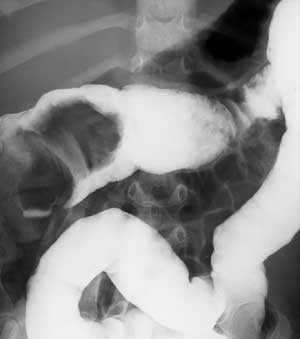

Рис. 3. Вовлечение кишечника при неходжкинской лимфоме.